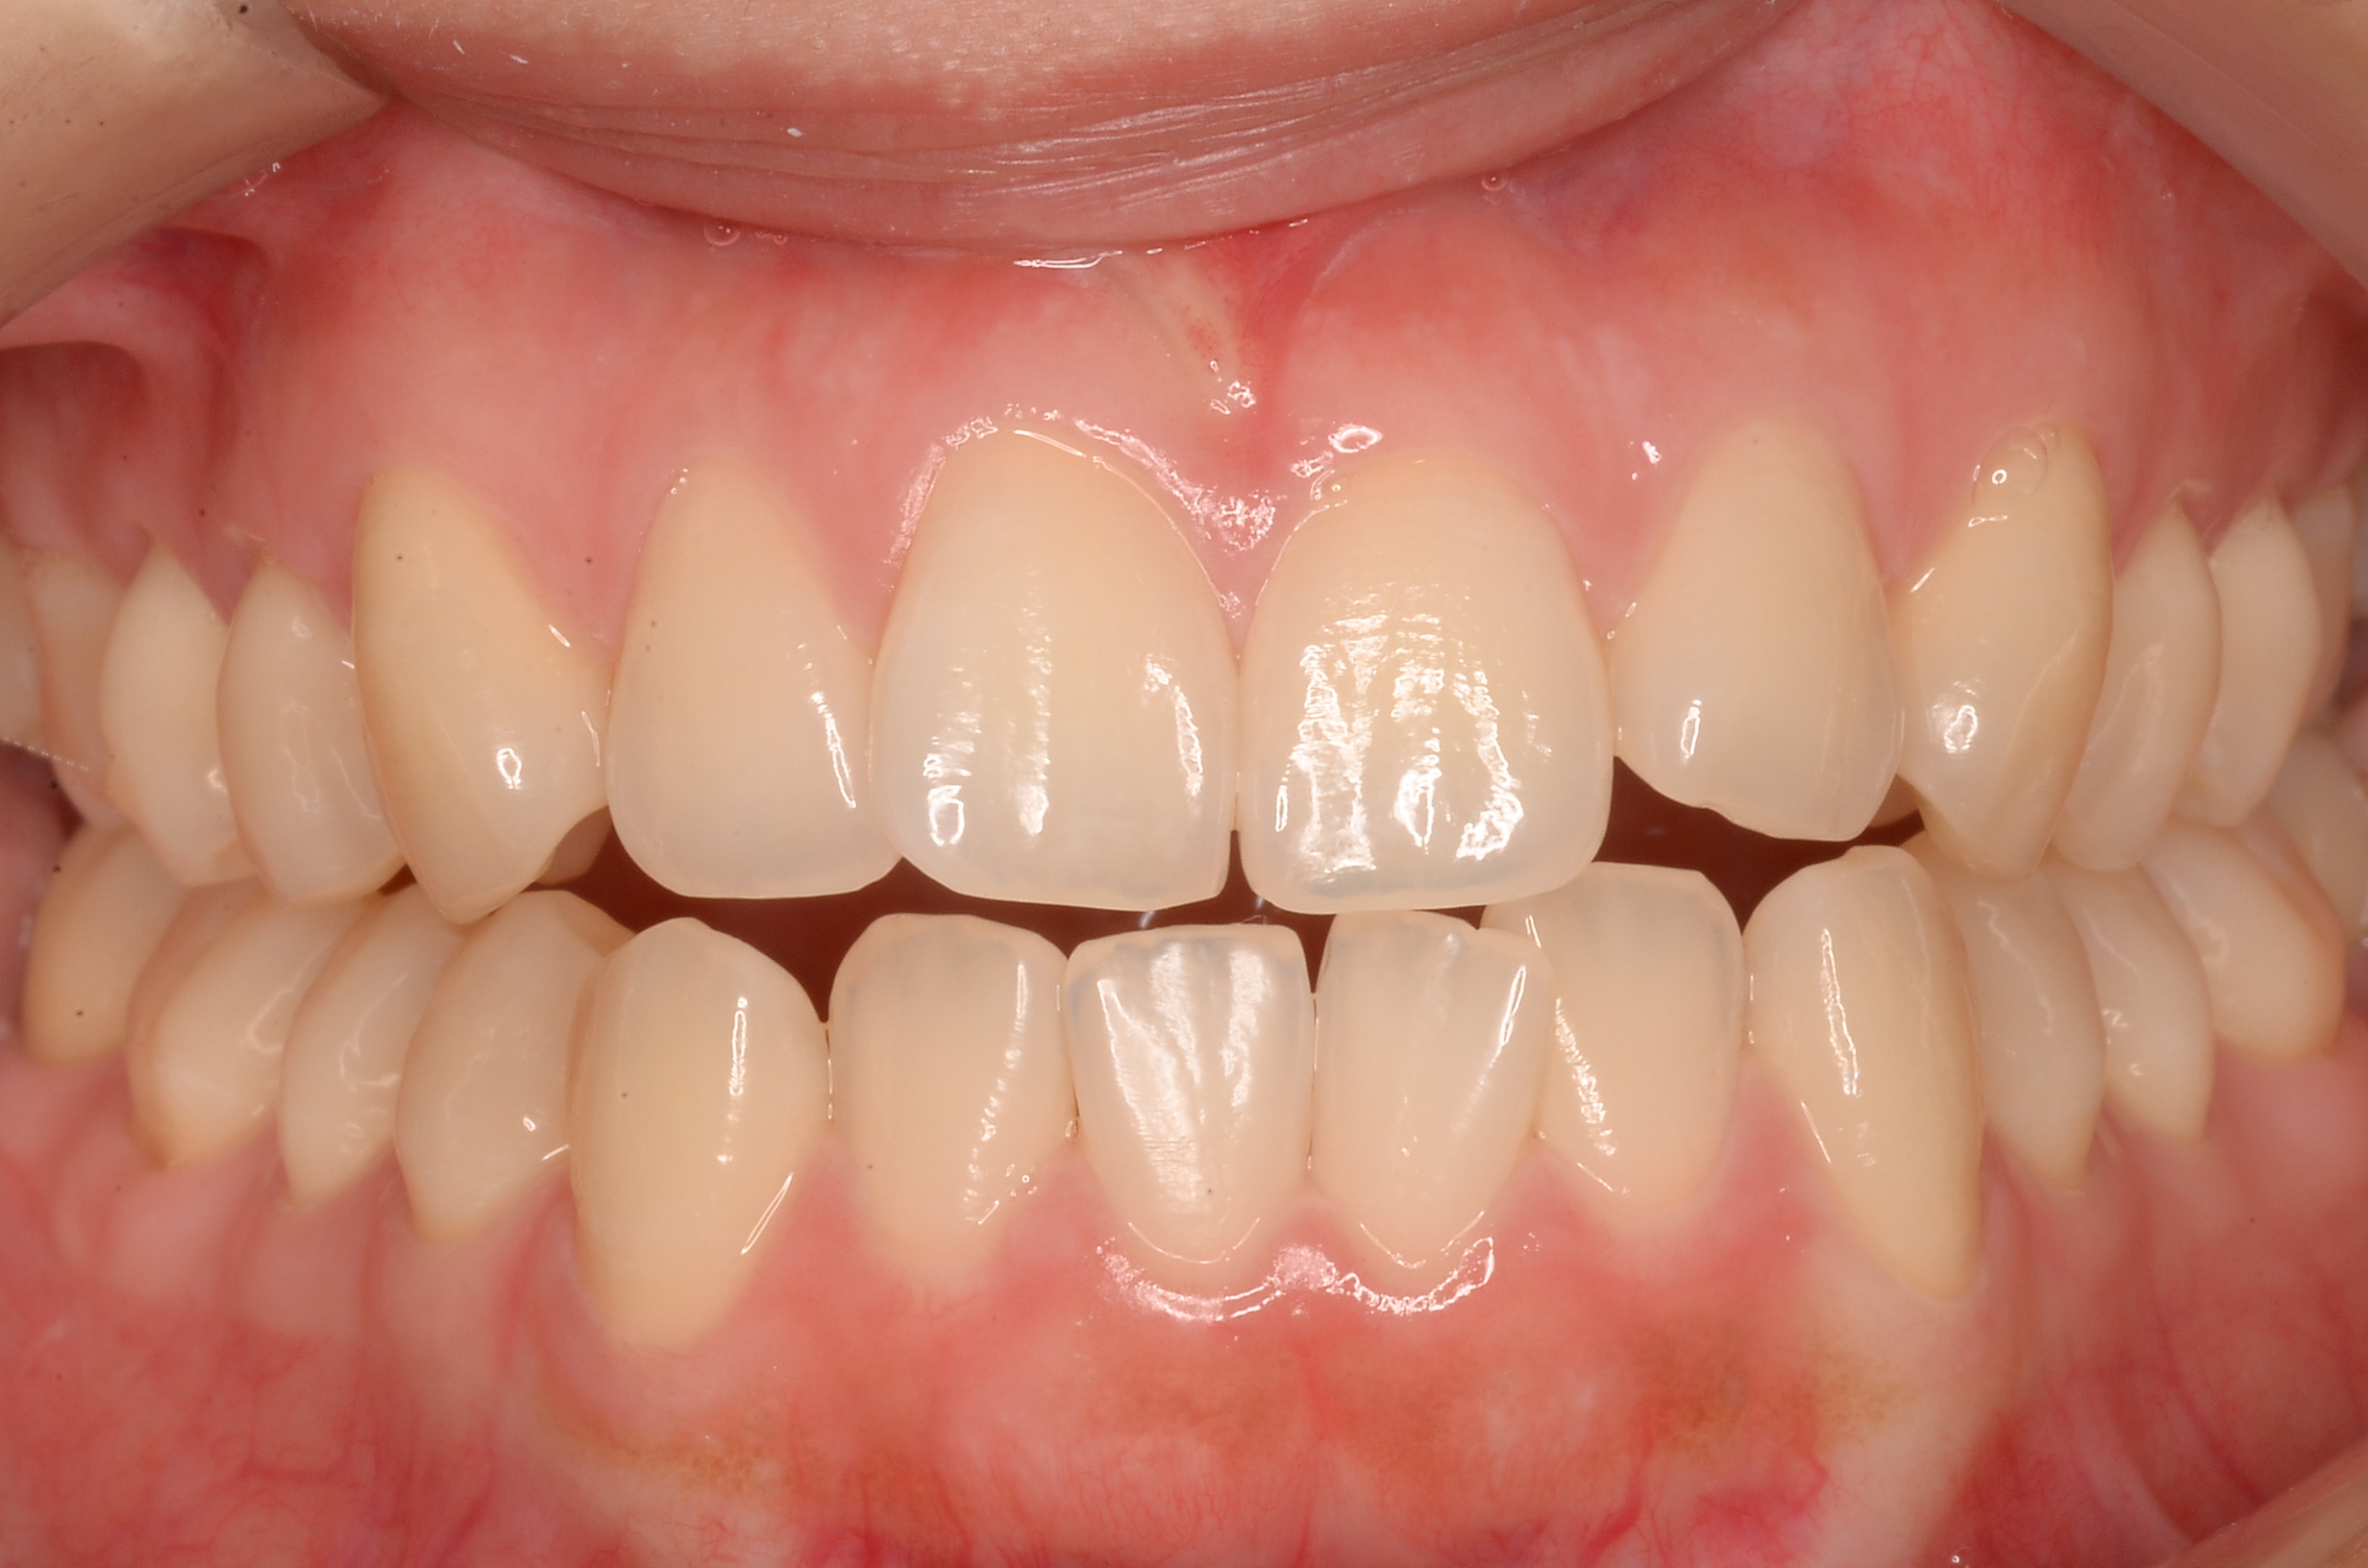

【27歳女性】7ヶ月で前歯の歯並びが改善✨マウスピース矯正(iGO)で手に入れた理想の笑顔

こんにちは!しんデンタルクリニックです🍀 心地よい春風が吹く季節になりましたが、皆様いかがお過ごしでしょうか。今回は「前歯の歯並びが気…more